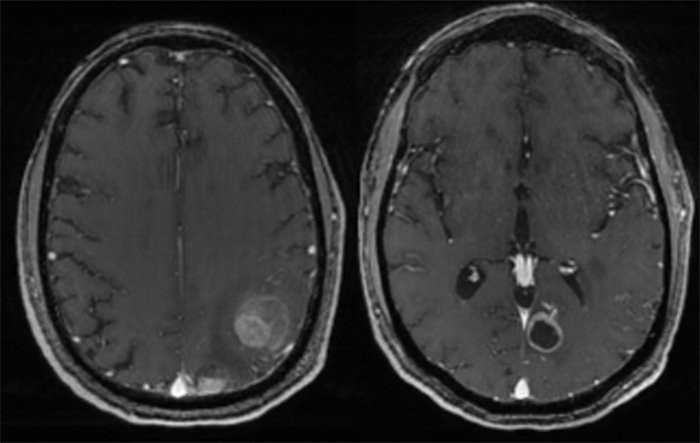

Brain metastases are the most common type of brain tumor in adults. They occur when cancer cells spread from another part of the body to the brain. Unlike primary brain tumors, which originate in brain tissue, metastatic tumors begin elsewhere, commonly in the lungs, breasts, colon, kidneys, or skin (melanoma). These cancer cells travel through the bloodstream or lymphatic system, forming tumors in the brain.